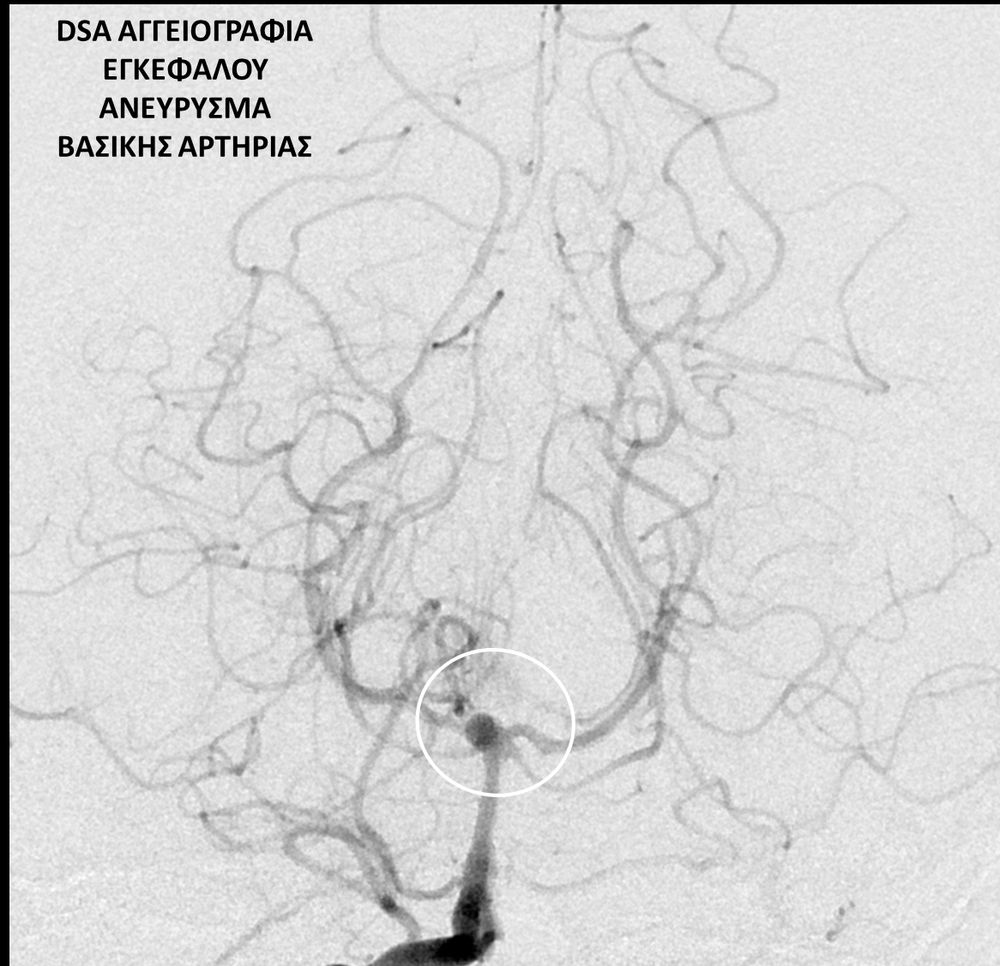

• Η ψηφιακή αγγειογραφία (DSA) αποτελεί την καλύτερη μέθοδο διάγνωσης των αγγειακών παθήσεων.Η αγγειογραφία γίνεται ως εξής: αρχικά παρακεντάται μια αρτηρία πρόσβασης, όπως η μηριαία αρτηρία στη βουβωνική περιοχή ή η βραχιόνια αρτηρία στο βραχίονα. Στη συνέχια προωθείται ένας καθετήρας προς την περιοχή του ενδιαφέροντος και γίνεται η έγχυση σκιαγραφικής ουσίας (σκιαγραφικού) με συνεχή λήψη «εικόνων» των αγγείων-στόχων.